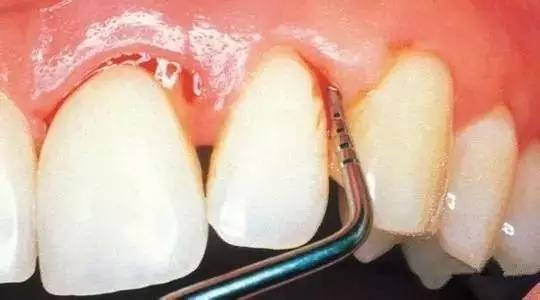

step2:中龋

当你吃糖的时候,感觉酸疼,你说:“没关系,只是一阵,一会就好了。”

牙医却说:“病菌已经抵达牙本质层了,牙齿已经有龋洞形成了,对酸甜食物较敏感,需要做修补。”